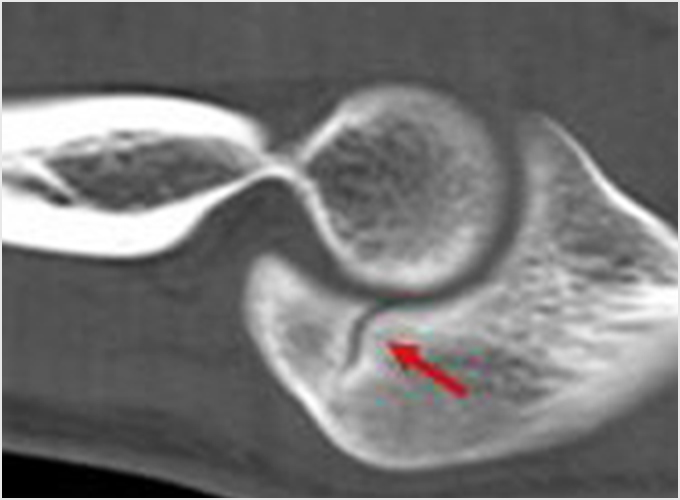

離断性骨軟骨炎(上腕骨小頭障害)

野球肘で最も重症になる障がいの1つです。ひどくなると関節軟骨の一部がはがれて関節ネズミとなったり、肘が変形して動きが悪くなったりします。初期に発見されれば投球禁止で治り、手術はしなくてもすむ場合が多いのですが、末期になると手術が必要となり、手術をしても肘の動きの制限や変形が残ってしまうこともあります。10歳前後で発症することが多いのですが、初期には自覚症状がないことが多く、13-17歳ごろにグラグラになった軟骨がはがれて痛みが出て初めて医療機関を受診されることもよくあります。 手術となった場合には骨の成長の度合い、病変の進行具合、病変の大きさなどにより手術方法が変わります。軟骨が安定している場合には軟骨を固定する手術を行う場合が多いです。軟骨がはがれている場合、病変が小さければ関節鏡を用いてはがれた、あるははがれかけている軟骨を摘出します(図4a)。病変の直径が1㎝以上であれば切開手術で膝の軟骨を病変部に移植します(図4b)。 最近全国各地で少年野球検診が行われるようになりましたが、一番の目的は離断性骨軟骨炎を早期に発見し、重症になる前に治療を行うことなのです。平成28年から多くの医師、理学療法士の協力により名古屋でも行われるようになりました。私も検診に参加し、エコーでのチェックを担当しました。およそ100人に1-2人の割合で発見されました。